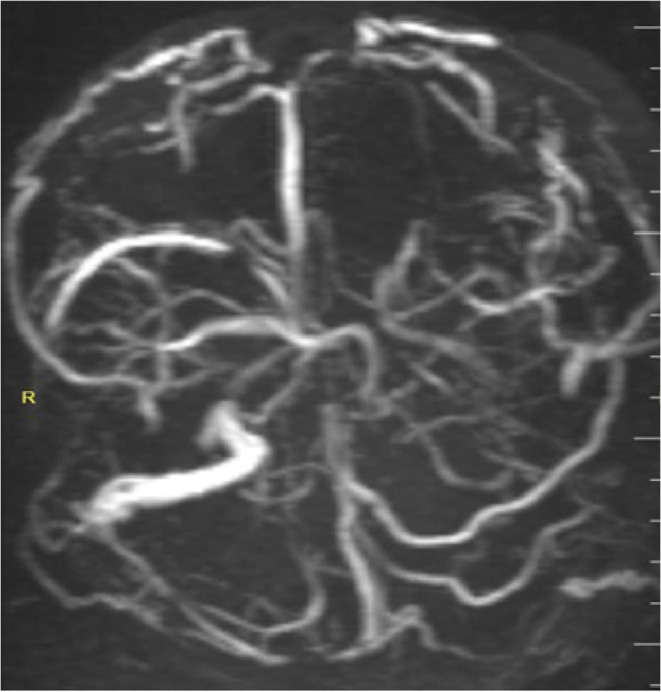

Cerebral sinus venous thrombosis (CSVT) is an uncommon and potentially life-threatening neurological disorder that is often missed because its clinical and radiological symptoms are not specific. Snake bites are a rare cause of cerebral venous sinus thrombosis that must be recognized and treated promptly to improve survival. Here, we present a case of a 30-year-old male patient who had cerebral venous thrombosis after snake bite in the rural area of southern Somalia. After close monitoring with anticoagulation, the condition of the patient improved and discharged from the hospital with full of consciousness. There are only a few cases reported in the literature of snake bites causing cerebral venous thrombosis.

Abstract Image